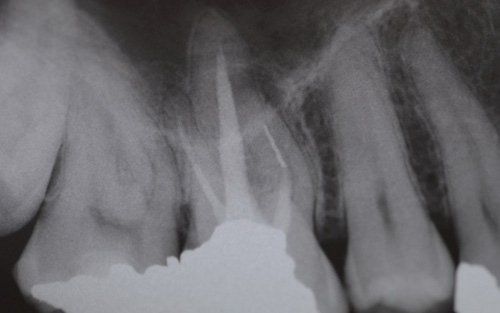

This treatment should be reserved for teeth that have irreversible pulp pathology (the nerve of the tooth) or an infection of the dental canals that has caused an abscess (acute apical periodontitis) or a granuloma (chronic apical periodontitis). While in the first two cases the tooth is very painful and the patient immediately seeks the dentist, the case of the chronic form is often silent, and therefore the patient may not notice anything for a medium to long period of time. In such conditions, it is only an X-ray image, taken during routine check-ups, that detects its presence. Root canal therapy can be completed by placing a latest-generation post inside the canal, as a means of retaining the material used for the reconstruction of the tooth. It will be up to the clinician to decide whether or not the restoration requires this additional anchoring system.